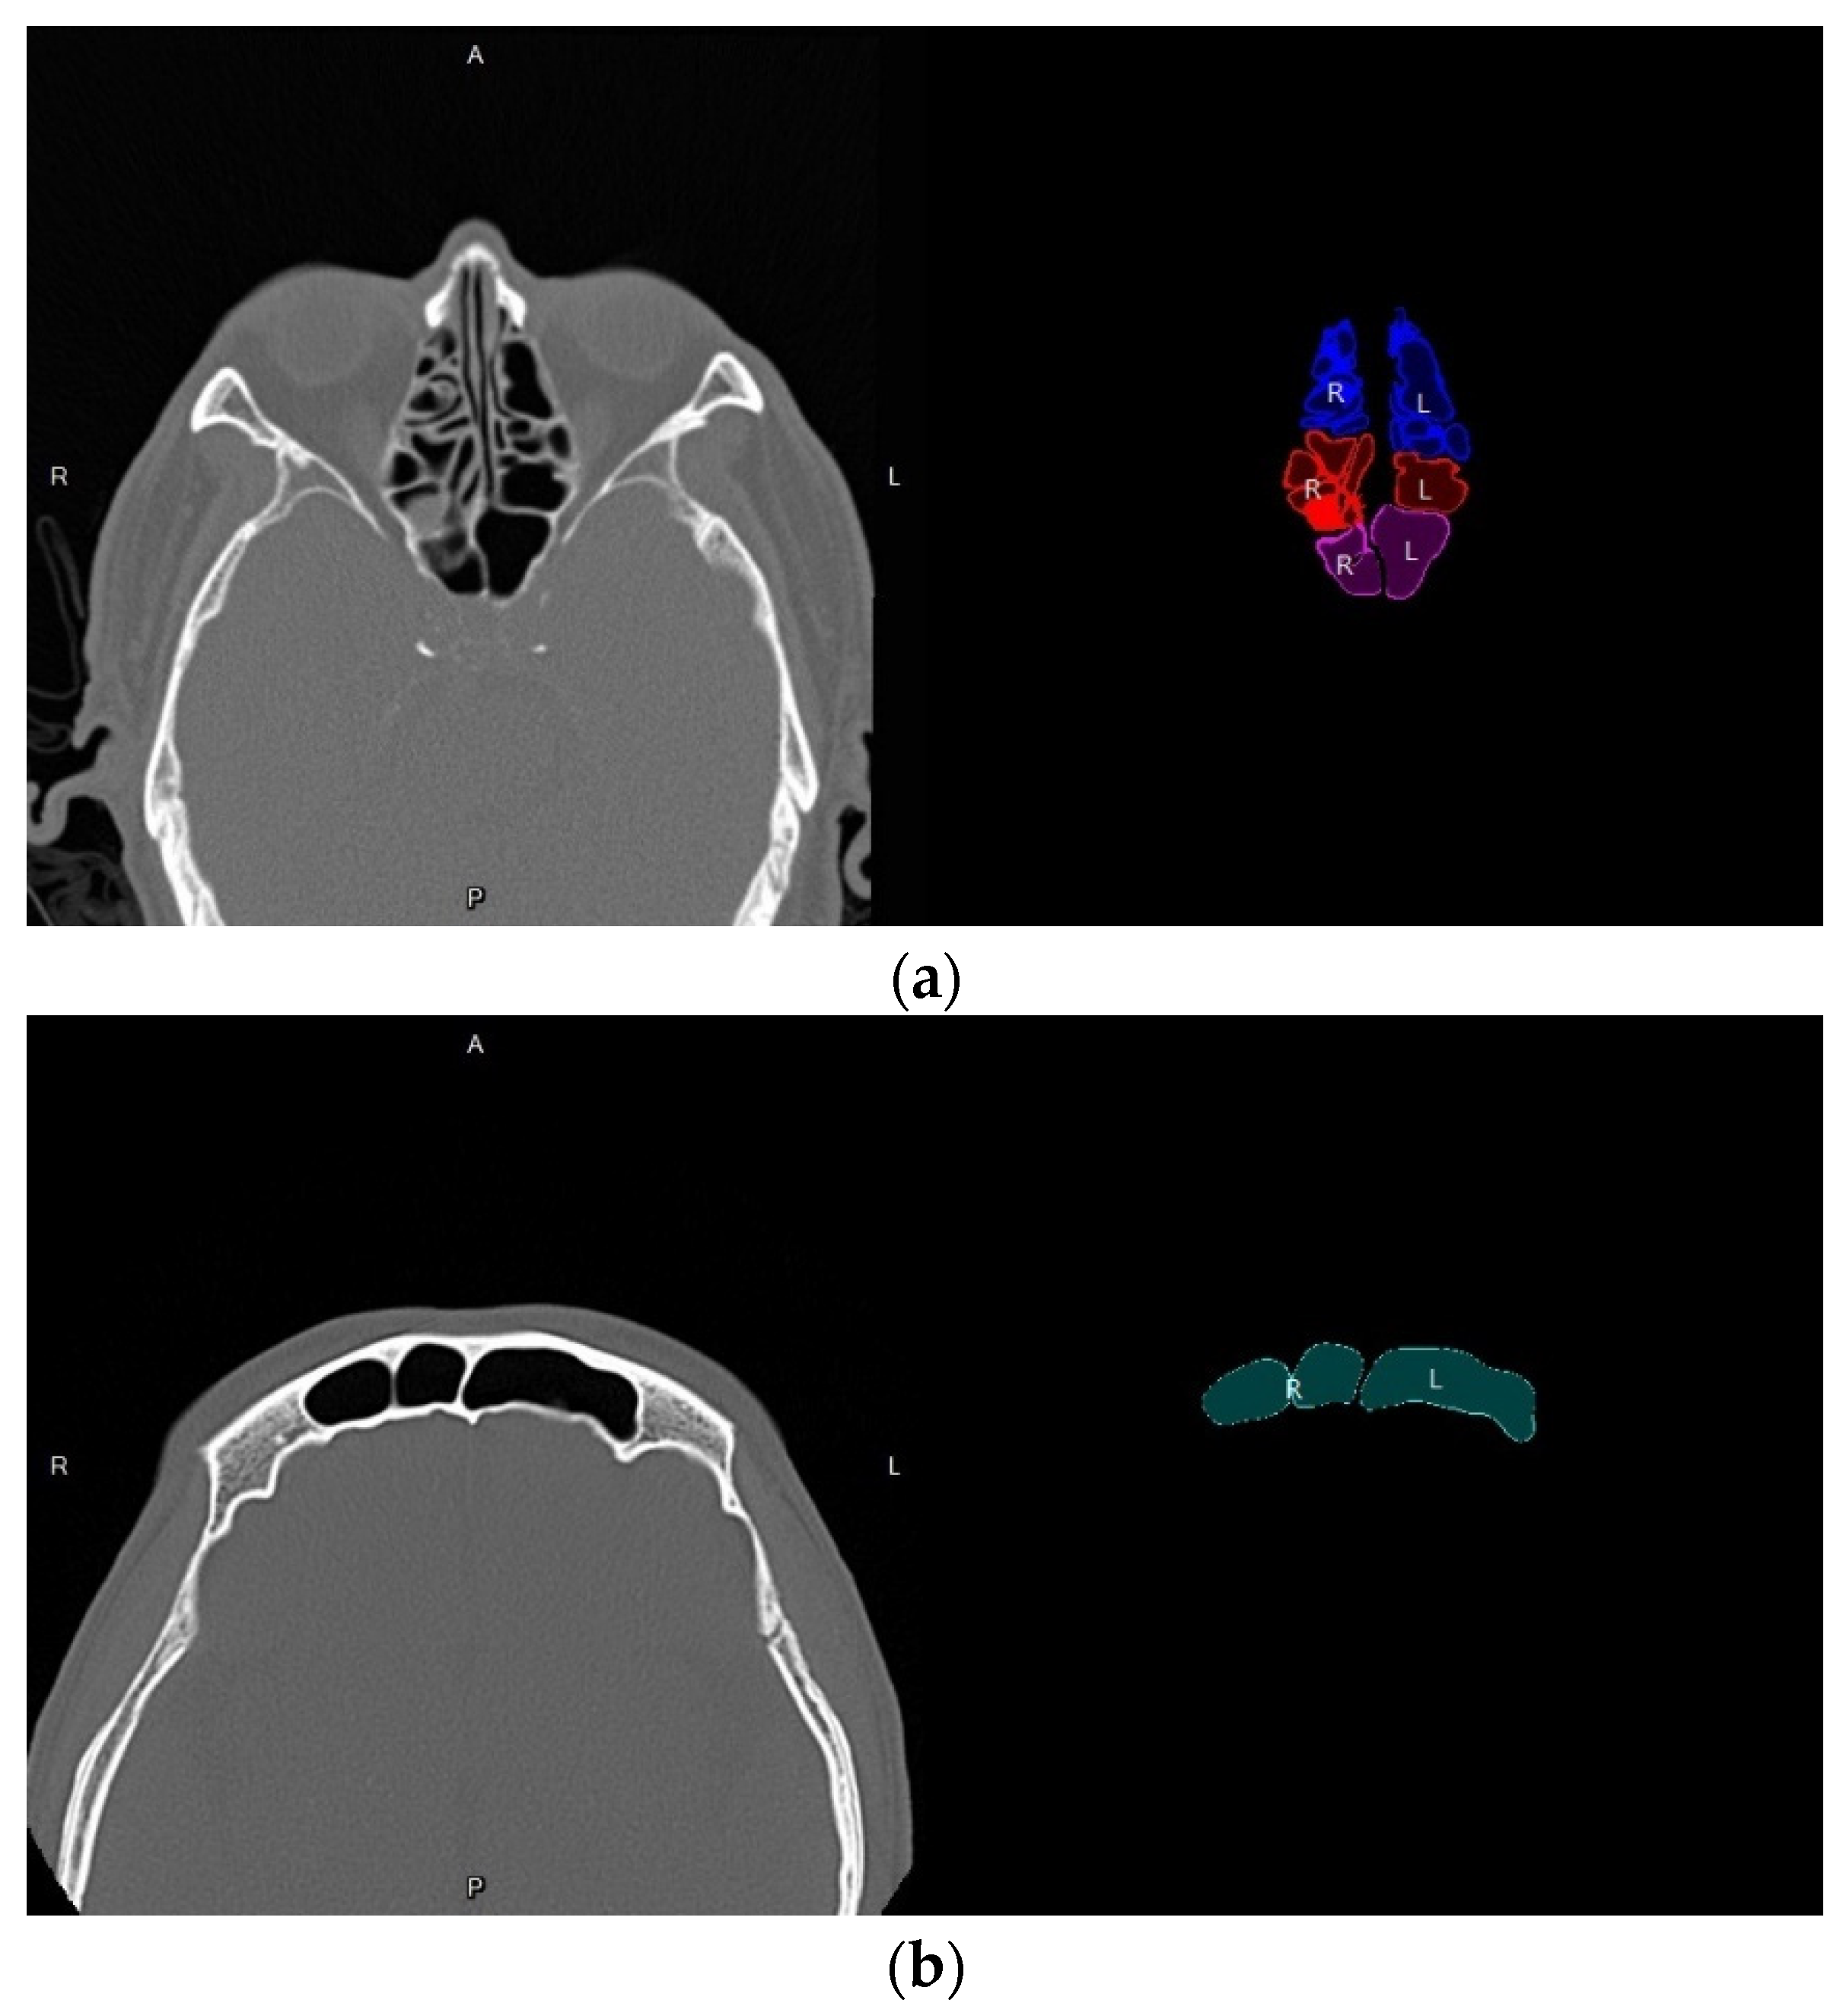

3.4. Volume Reconstruction

3.4.1. Morphology

3.4.2. 3D Reconstruction